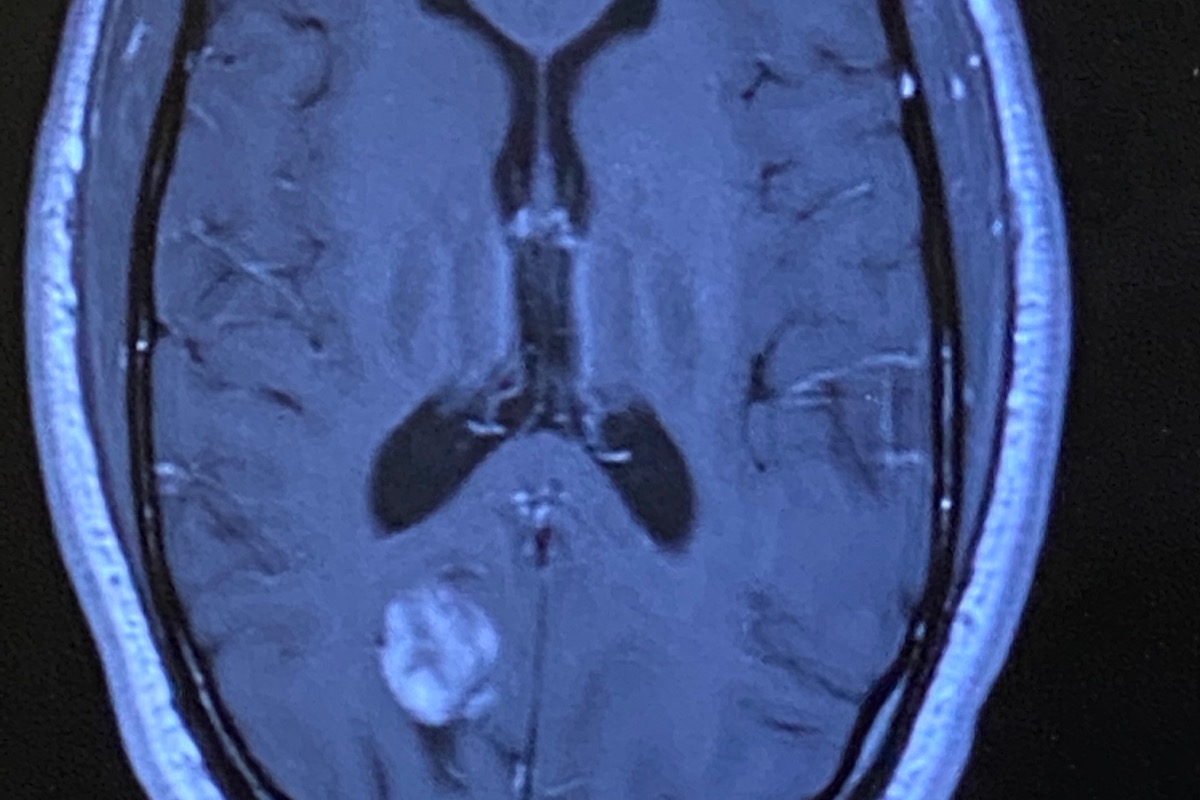

32+ Brain Cyst Surgery Recovery Time Images. After brain surgery, it will take time for the patient to return to his/her usual level of energy. Eea surgery offers the benefits of no incisions to heal, no disfigurement, and a faster recovery time.

Recovery after brain aneurysm surgery can take months or longer and involves rehabilitative therapy and more. The amount of time it takes for you to recover depends on how your surgery was done and if you received stitches. Brain surgery recovery time depends on the area of the brain that is affected, the amount of brain affected, the strength of the individual and possible complication during surgery.

The amount time it take to recover from brain surgery?mind medical procedure is applied to patients to keep up a kind of harm or injuries inside it will most likely grow, you need surgery in order to remove the cyst, if it is too large, you will most likely develop seizures, tumors, and within time, die. Brain surgery recovery is a gradual process and can take two months, and sometimes more. This is an introduction of the upcoming series: There is a range in the amount of time it takes to recover, and the duration of your recovery depends on the type of brain aneurysm surgery you had, whether your aneurysm ruptured.